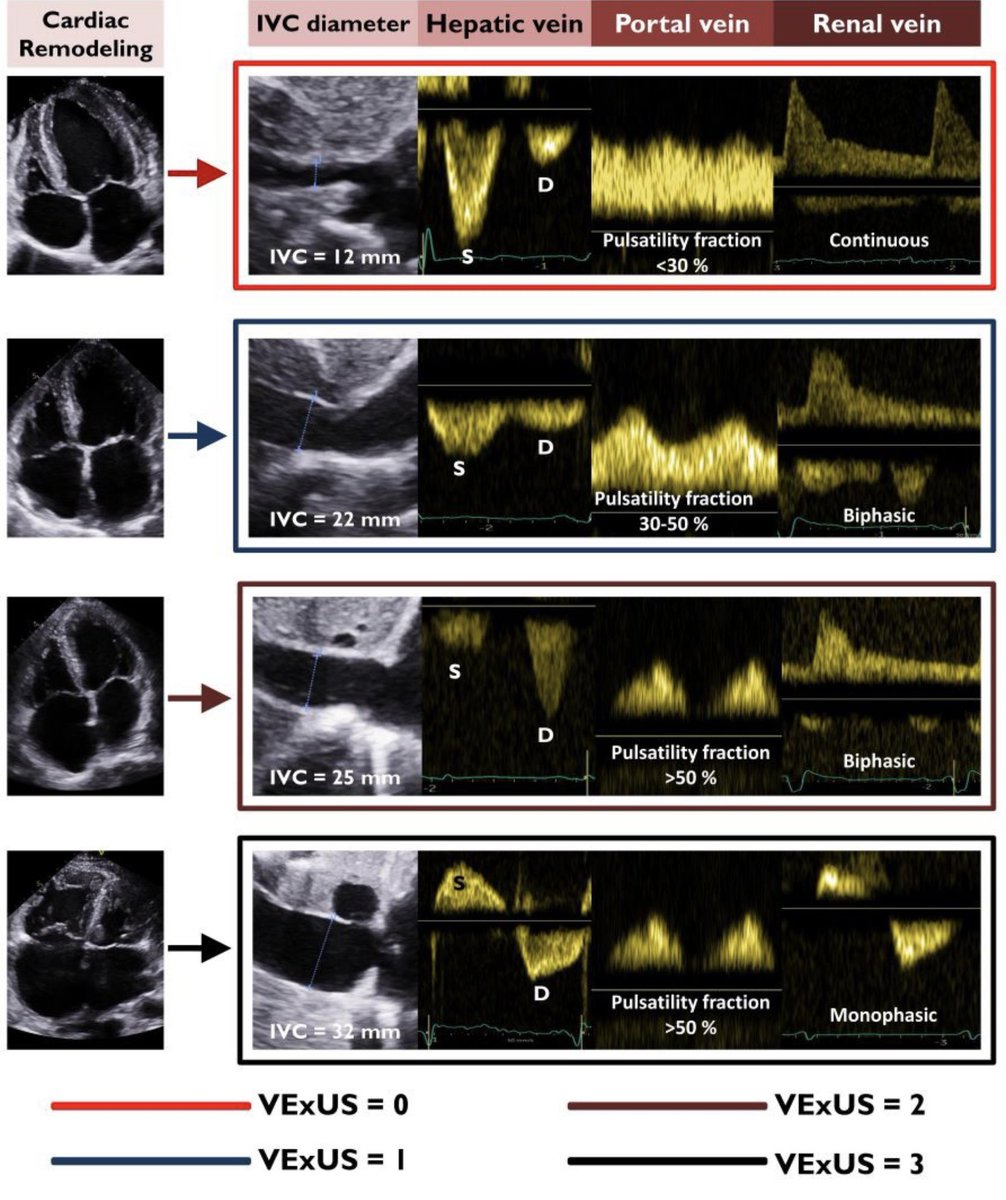

HFpEF in CKD ca. 2023 from Kidney Medicine #Nephpearls #Cardiorenal ๐๐ผ pubmed.ncbi.nlm.nih.gov/31476759/